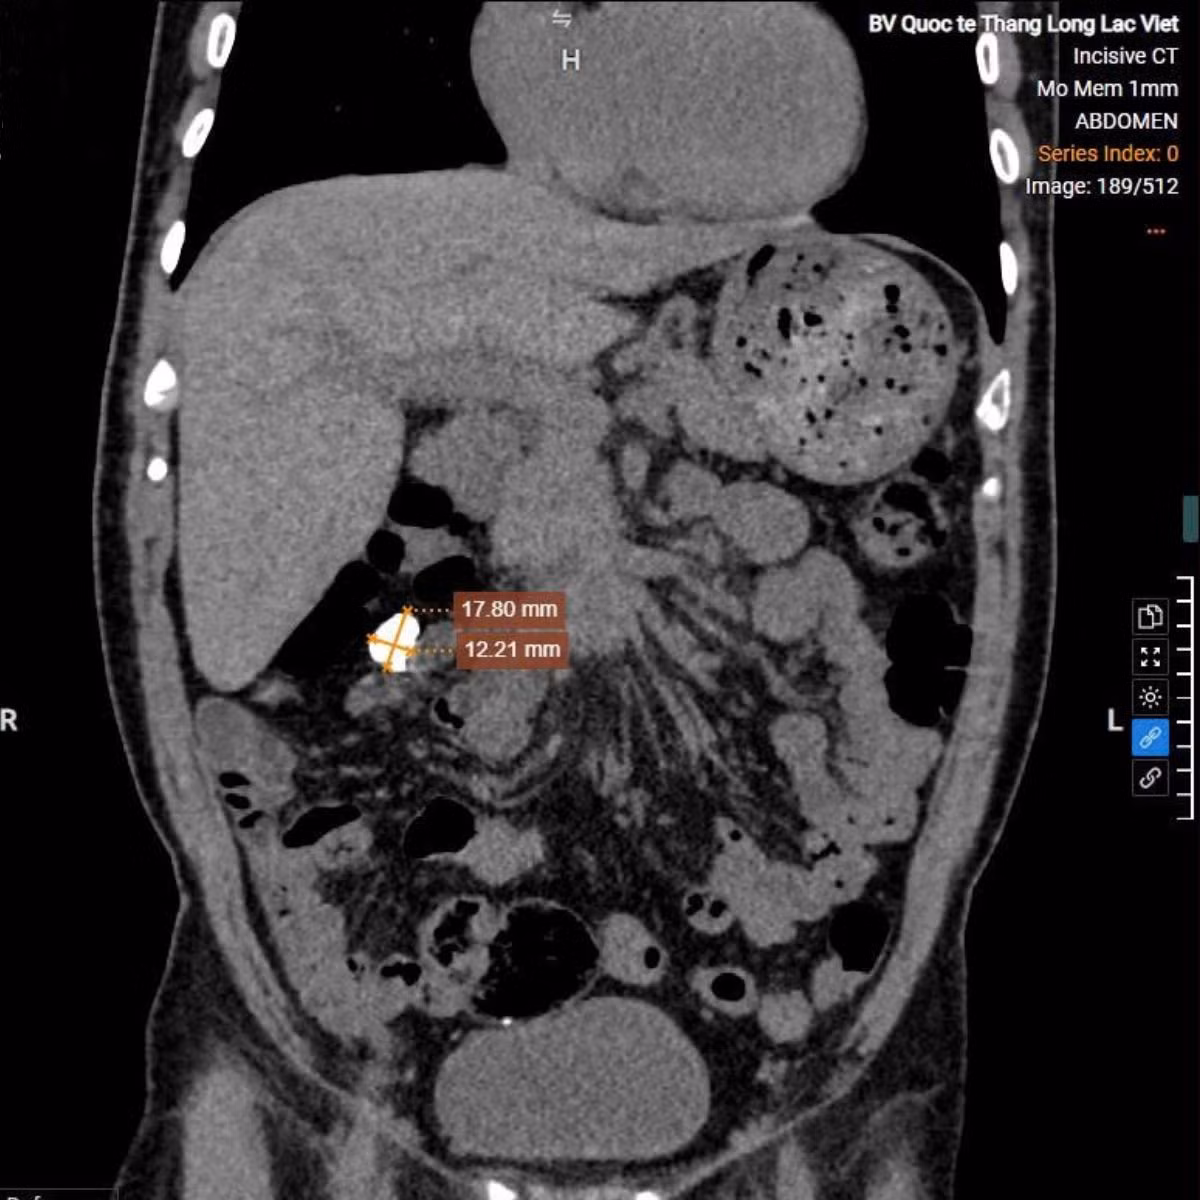

Để mang lại kết quả chính xác nhất, chuyên gia đã chỉ định bệnh nhân T. thực hiện chụp cắt lớp vi tính (CT) ổ bụng. Hệ thống CT 128 dãy hiện đại với khả năng tái tạo hình ảnh siêu sắc nét đã đưa ra kết quả hoàn toàn bất ngờ - không phải sỏi thận như chẩn đoán suốt nhiều năm qua mà là nốt vôi hóa thành ổ bụng (Kích thước ~ 15x10mm).

Hình ảnh trên phim chụp CT 128 dãy ổ bụng - Ảnh BVCC

Kết quả chụp ổ bụng của bệnh nhân - Ảnh BVCC